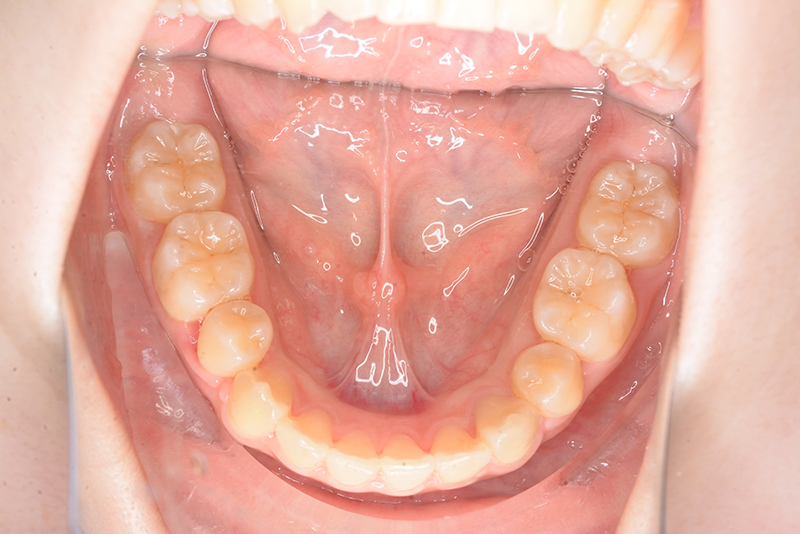

| 口腔内所見 | over jet 3.8mm、over bite 30mm、臼歯関係I級、上下顎前歯部に叢生が認められ、下顎正中は右側へ4.5mm偏位していた。左上5はCRの治療痕が認められた。 |